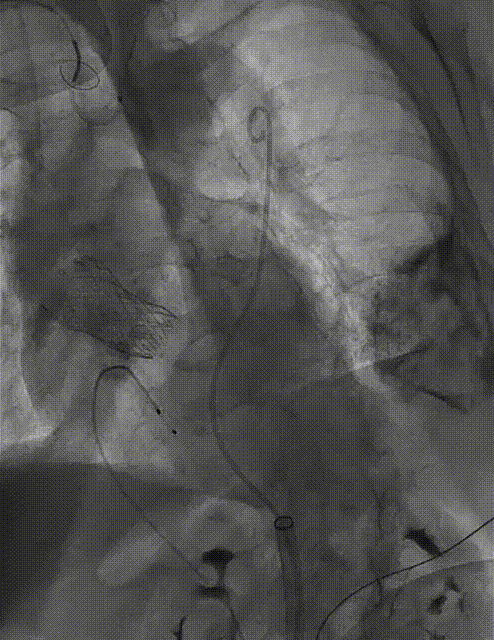

宋光远教授 首都医科大学附属北京安贞医院(点击查看专家详细简历) 技术革新不止,创新求索不辍:一切从患者出发,不断追求创新是内心的坚定。当年‘ALL IN ONE’的探索,正是怀揣着这份初心 —— 通过整合器械与操作,将入路创伤缩至最小,让患者在微创中更快康复,这是技术对患者的温柔承诺。而术中脑保护,是我们为安全筑牢的另一道防线。 此次预装干瓣的临床应用,让我们直面瓣膜“耐久性“临床困境,期待创新技术助力全生命周期管理! 病例概览 患者病史 患者因 “劳力性呼吸困难半年余,加重 20 天” 入院。高血压病史 20 年,最高血压 160/110mmHg;高脂血症病史;反流性食管炎。 超声提示:主动脉流速 Vmax 4.66 m/s,平均压差 53mmHg,左室射血分数(LVEF)40%; 超声诊断:主动脉瓣狭窄(重度)、主动脉瓣反流(轻中度)、二尖瓣狭窄(轻度)、二尖瓣反流(轻度)、三尖瓣反流(轻中度)、左房增大,左室肥厚。 术前CT 瓣环(Annulus)直径:22.9mm,左室流出道(LVOT)直径:周长径 23.8mm;总钙化负荷1239mm³(HU850),钙化集中于无冠窦,且蔓延至 LVOT,呈重度钙化表现;LVOT-Annulus 呈微直筒型,瓣上限制较重。左冠脉开口高度略低,瓣叶不长、窦部空间较大,结合钙化分部情况,预估双侧冠脉遮挡风险较低。室间隔膜部较短(2.4mm)有一定PPI风险,心室大小可,心脏角度64°,升主长度短于胶囊腔长度,同轴有一定困难。 · 造影角度及入路情况:主动脉弓角度可,但降主动脉折曲明显,双侧髂股动脉存在粥样硬化。 手术策略 采用 “极简式” 手术方案:18/20mm 球囊预扩张,植入金仕生物 Prostyle-A 预装干瓣(AV 26),配合长鞘,同时植入脑保护装置以降低卒中风险。 手术过程 球囊预扩:18号球囊预扩 输送系统顺利过弓跨瓣: 瓣膜植入:工作位观察位置适宜,完成植入。 术后即刻:术后造影显示瓣膜位置佳 入路与血管:撤出大鞘后检查,降主动脉仍存在较大弯折;入路闭合良好,无明显出血或血管并发症。 Prostyle A®预装干瓣——助力临床最优化解决方案: √ Mircro-EX™专利抗钙化技术:极简式预装干瓣,不使用戊二醛浸泡,减少钙化成因,干态存储的瓣膜术中无需清洗瓣膜,减少组装步骤,缩短手术时间,尤其适合复杂病例中的高效操作; √ 平衡的径向支撑力:重度钙化的患者,形态展开良好,在横位心等复杂情况下实现稳定锚定及释放; 专家简介 苑飞 首都医科大学附属北京安贞医院(点击查看专家详细简历) 姚晶 首都医科大学附属北京安贞医院(点击查看专家详细简历) · END ·